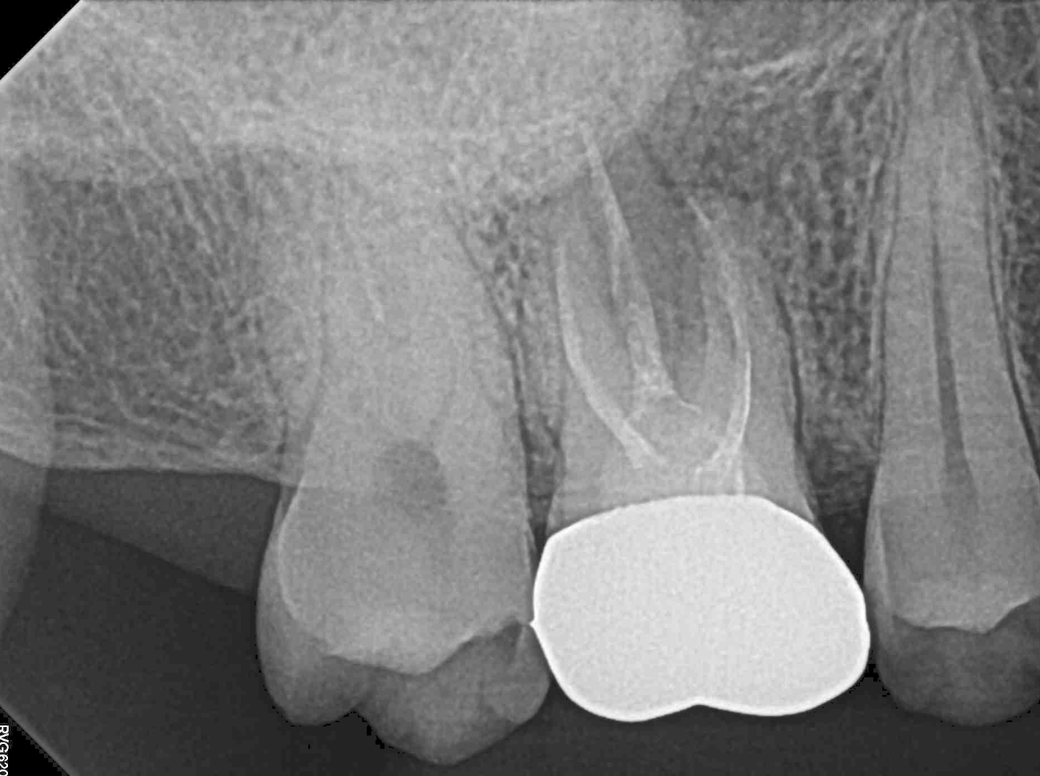

2. 두 치과 모두 뿌리염증이 있다고만 하고 어느 정도인지는 구체적으로 설명을 안 해줬습니다. 사진 상으로 어떤 정도인지 궁금합니다(비교용으로 그간 찍었던 사진을 같이 첨부했습니다) 최근 파노라마를 보면 오른쪽 신경 옆쪽으로 약간 검은 음영이 있는데 이게 뿌리 염증일까요?

그리고 최근 치근단 사진을 보면 신경에서 하얗게 치료된 부분 위로 검은 부분이 보이는데 신경치료가 완전하게 되지 않은 게 맞을까요?

23년 6월 파노라마, 치근단

-사진상으로 보면 재신경치료를 하시는것보다는 발치를 해야될 가능성이 높아 보이네요.